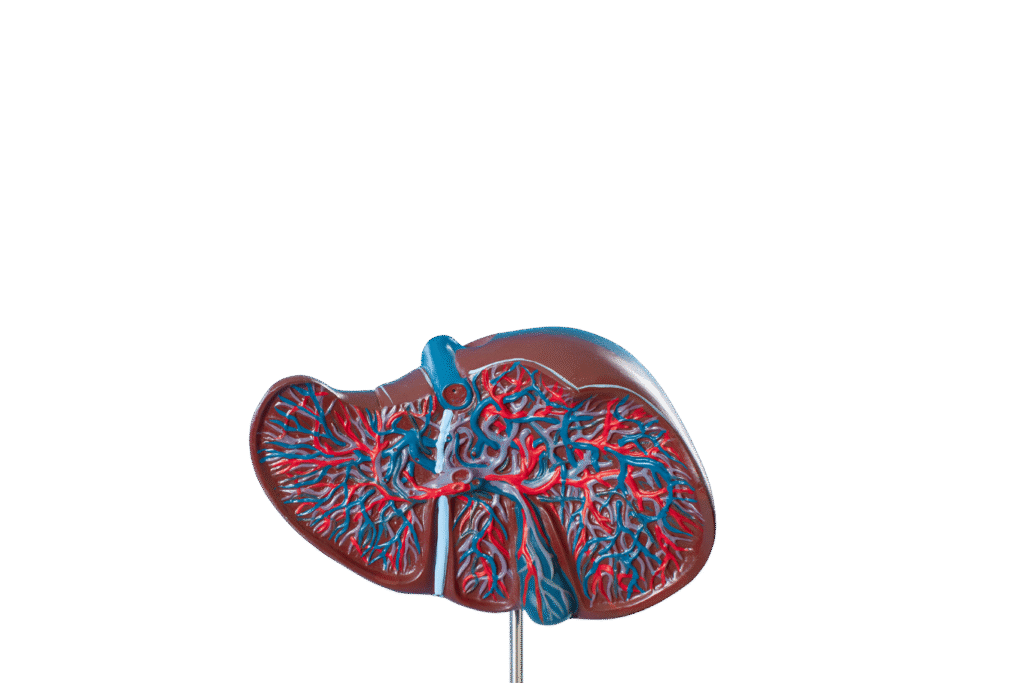

Liver transplant is a complex but life-saving procedure for patients with severe liver disease, liver failure, or certain liver cancers. It involves replacing a diseased liver with a healthy one from a living or deceased donor. At our Liver Transplant and HPB Surgery Care center, we provide comprehensive care for both adults and children, ensuring safety, precision, and excellent outcomes.